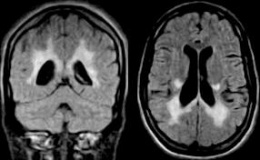

Leucodistrofia metacromática. Es un trastorno genético que empeora lentamente con el tiempo y afecta los nervios, los músculos, otros órganos y el comportamiento.

La leucodistrofia metacromática (LDM) generalmente es ocasionada por la falta de una enzima importante denominada arilsulfatasa A. Debido a la ausencia de esta enzima, unos químicos llamados sulfátidos se acumulan y causan daño al sistema nervioso, los riñones, la vesícula biliar y otros órganos. En particular, los químicos causan daño a las vainas de mielina que rodean las neuronas.

- Resonancia magnética